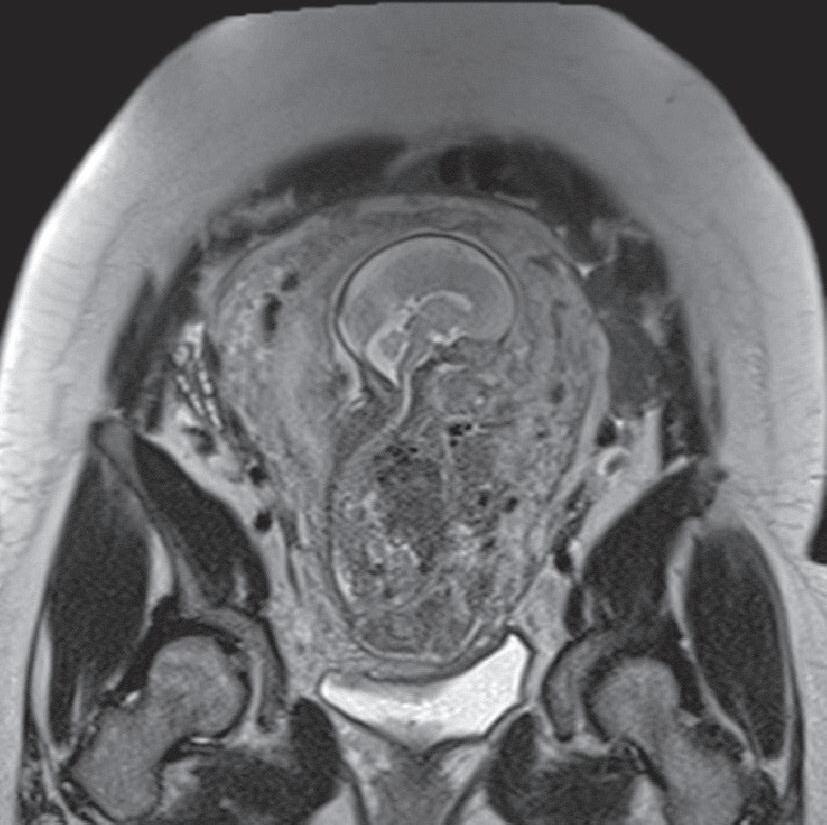

A perinatologia, também conhecida como medicina materno-fetal, é uma subespecialidade dedicada ao estudo, ao diagnóstico e ao acompanhamento de gestações de alto risco, com atenção tanto à saúde da gestante quanto ao desenvolvimento do feto. Nesse campo, os métodos de imagem desempenham papel essencial na avaliação da anatomia e da fisiologia do feto, na identificação precoce de malformações, no planejamento terapêutico e no aconselhamento à família.1,2

O exame por imagem em perinatologia evoluiu significativamente nas últimas décadas, acompanhando os avanços tecnológicos que permitiram melhor resolução, maior rapidez e mais segurança. Atualmente, a ultrassonografia (USG) e a ressonância magnética (RM) são as principais modalidades, complementadas em casos específicos por radiografia, tomografia computadorizada (TC) (de uso restrito, devido à radiação ionizante) e, mais recentemente, técnicas emergentes de inteligência artificial (IA) aplicadas à análise de imagens.3,4